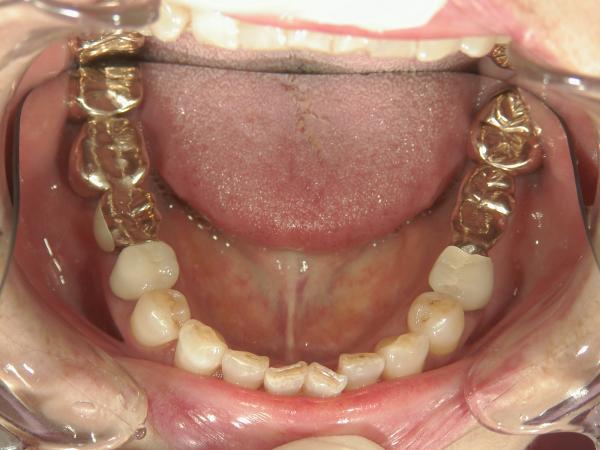

歯冠修復

被せ物や詰め物には、素材や保険内・外など様々な種類があります。当院では、お悩みや症状、ご予算・ご希望に合わせて最適な治療プランをご提案し、お客様にお選びいただいております。まずはお気軽にご相談ください。

・ゴールドクラウン

金合金や白金加金など安定した貴金属を歯科修復材とした被せ物です。金属色にはなりますが、しなやかなで歯との相性が良く、歯科修復材として高く評価されています。奥歯(臼歯)など目立たないところにお勧めしています。

【料金】ゴールドクラウン 120,000円(税別)